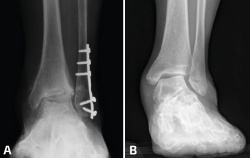

Cualquier alteración de la transmisión de cargas de la extremidad inferior puede producir una sobrecarga mecánica anormal y mantenida en el tobillo que puede llevar a una artrosis asimétrica. Cuando la transmisión de cargas se concentra en el área lateral del tobillo (región cóncava de la deformidad) se producirá un desgaste asimétrico de esa zona del tobillo (Figura 2).

Figura 2. A: alteración de cargas pre-osteotomía; B: osteotomía supramaleolar de cierre medial.

En los casos de malalineamiento en valgo, la OTT-SM debe lograr un efecto varizante. Esto se puede lograr con diferentes modelos de OTT; la más comúnmente utilizada es la OTT en cuña de cierre medial, que se realiza mediante un abordaje medial en la tibia distal, asociado o no a OTT de apertura en peroné (Figura 2).